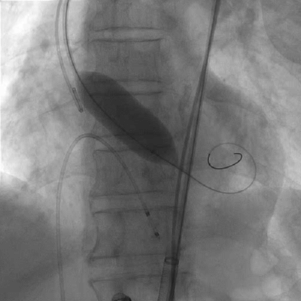

患者麻醉方式采取全麻,建立静脉通路后,穿刺左侧股动脉,建立副入路。在超声引导下精准穿刺右股动脉及股静脉,预埋两把ProGlide缝合器,置入20F动脉鞘管,漂浮电极经股静脉送至右室心尖。跨瓣成功后,将Lunderquist导丝送入左心室, 23mm球囊预扩张,Venus-A 29瓣膜精准定位并释放,术中造影及超声反馈良好,瓣膜形态良好,结果满意。

球囊预扩